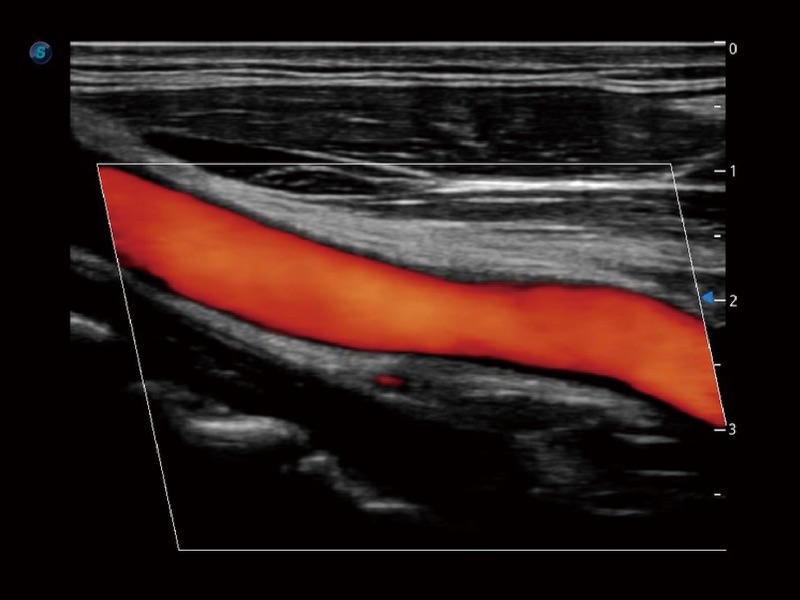

• 血管内中膜自动测量 Auto IMT

血管内中膜的厚度值是预测心血管疾病风险的重要指标,Auto IMT可以实现血管近场和远场内中膜厚度的自动测量,为临床提供快捷有效的诊断工具。

• 心血管应用